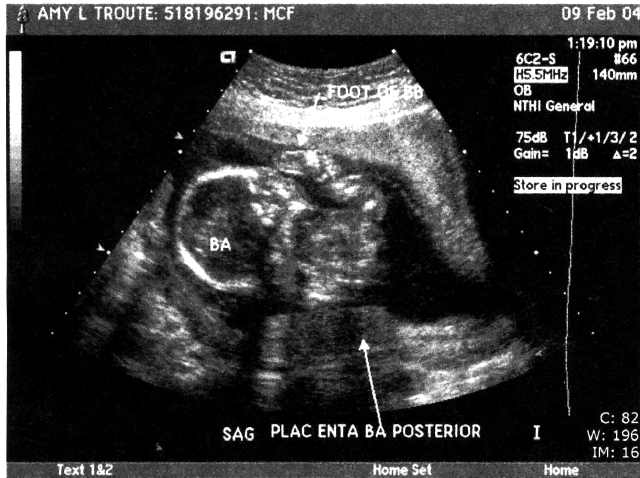

| We had our BIG ultrasound on February 9. Here are a few of the 111 pictures that were taken (everything from areas of the brain to little tiny kidneys) in our nearly 2-hour appointment (click the pictures to get a larger view – note the one where Baby A’s foot is right above Baby B’s head – so cute!!). The babies were moving so much that the tech had to literally hold them down with the ultrasound wand to get the detailed pictures she needed! Talk about uncomfortable!! Whew!! We were thrilled to hear that they’re developing perfectly – measuring in at 14cm and 9oz each!! They even bumped my due date up a week since the babies were measuring bigger than normal – music to our ears!! We’re still shooting for late June… I’d be at 36 weeks on my birthday – I’d love to share June 17 with the twins…or our anniversary June 23, or Father’s Day… ;o) We heard the heartbeats at a doctor’s appointment on 2/18 and my “theory” of their different heart rates signaling “boy and girl” was blown… In each of our past appointments there was a 10-15 beat difference between the two, but this time both were right at 160 beats per minute. I guess Reese is right – I really have no idea who’s in there! This week (2-16 to 2-20) I’ve started to really feel the babies moving! They’re especially active from 2-5 in the afternoon… makes it so hard to concentrate! I love it! I can't imagine how it's going to feel once they weigh more than 9 or 10oz each... Two 4 or 5lb kiddos in there packing on the pounds, rolling around and sticking their feet in each other's faces... Hahaha! What an image!! And the thought of them being most active at night... The adventure is only beginning!" |